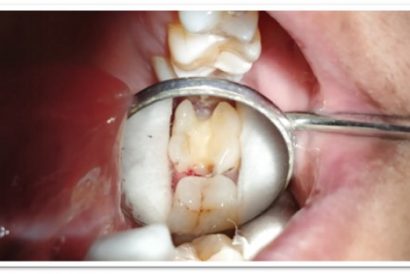

Patient Name:Akshay Gharat

Tooth Involved :16

Diagnosis :Caries Involving Enamel And Dentin Mesiocclusally

Treatment :Class Two Direct Composite Restoration Using Nanohybrid Composite

Before

After